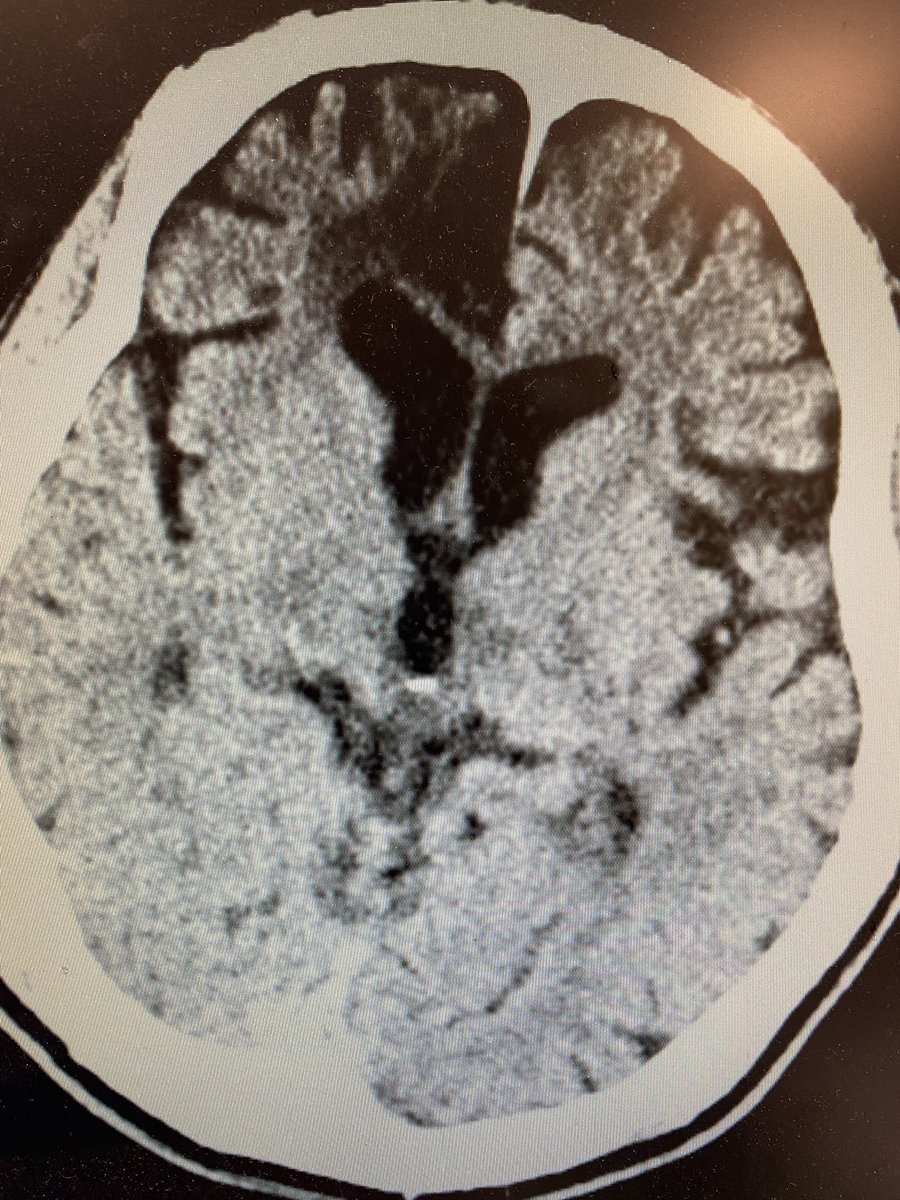

Initial CT head reveals prior right frontal encephalomalacia but no hemorrhage. CTA does not reveal any large vessel occlusion. EEG reveals slowing, generalized, excess beta, no epileptic Discharges or seizures 4/x

What is your diagnosis now? Only one left is serotonin syndrome which would fit except for the right pupil… Repeat ct now makes diagnosis clearer and mri confirms 5/x

You got it! Artery of Percheron stroke leading to depressed mental status and nuclear IIIrd nerve palsy! Here is a first reference bmcneurol.biomedcentral.com 8/x

AOP infarcts affect bilateral para median thalamus and may also affect the midbrain and/or anterior thalamus. Presentation often involves depressed mental status, EOM deficits, aphasia, dysarthria, amnesia, ataxia, dystonia, weakness and sensory changes 10/x